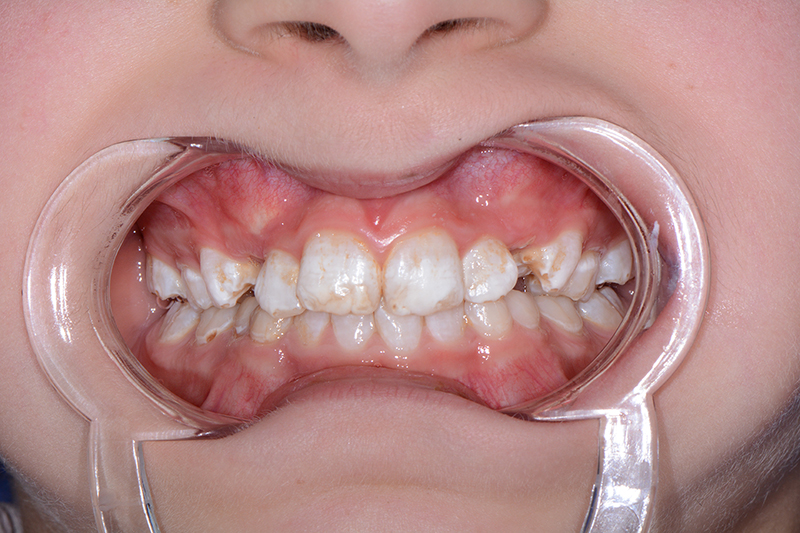

Selon le type de défaut principal, l’AI peut être qualifiée d’hypoplasique, d’hypominéralisée ou d’hypomature. Plusieurs formes peuvent coexister dans une même famille, chez un même patient, voire sur une même dent, ce qui complique le diagnostic. L’expression des nombreux gènes, et l’implication de différentes protéines expliquent ces formes d’AI si différentes (Tableau I).

Les conséquences cliniques des AI sont multiples et potentiellement sévères :

• dyschromie : c’est l’anomalie de teinte des dents, par exemple des taches blanchâtres, un aspect jaunâtre, voire brunâtre des dents

• hypersensibilité (douleurs au froid, au brossage, à la mastication par exemple)

• pertes de substance.

La malocclusion est fréquemment associée aux formes hypoplasiques et se manifeste principalement par une infraclusion antérieure (« béance »), qui peut être sévère, venir encore aggraver le préjudice esthétique et engendrer des difficultés de mastication et d’élocution.

Dans la plupart des formes d’AI, l’aspect esthétique est fortement compromis. En effet, l’émail étant très fin, voire absent, la couleur de la dentine devient apparente, conférant à la dent une teinte jaunâtre voire brunâtre. Enfin, l’usure prématurée de l’émail et les pertes de substance associées à une rétention accrue de plaque sont susceptibles d’augmenter le risque carieux.